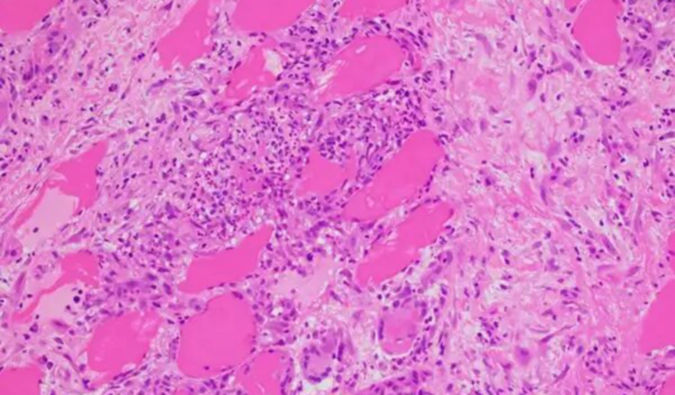

毒理学研究

HJC黄金城平台提供全面的毒理学研究服务,用于评估药物化合物的安全性特征及潜在风险。我们的专业团队紧密配合客户,根据监管要求和项目的具体需求,量身定制研究方案。

非GLP与GLP毒理学研究

• 单次给药毒性试验(啮齿类和非啮齿类)重复给药毒性试验(啮齿类和非啮齿类)遗传毒性试验免疫原性试验毒代动力学局部毒性试验(溶血、过敏、刺激性试验)致癌性研究新给药技术的毒理试验:吸入毒理ADC 安全性评价安全药理试验:中枢神经系统研究、心血管系统(犬和猴的遥测和非遥测技术)、呼吸系统、hERG生殖毒性试验[生育力与早期胚胎发育毒性试验(生殖I段)、胚胎-胎仔发育毒性试验(生殖II段)、围产期毒性试验(III 段),或各段组合式试验。]